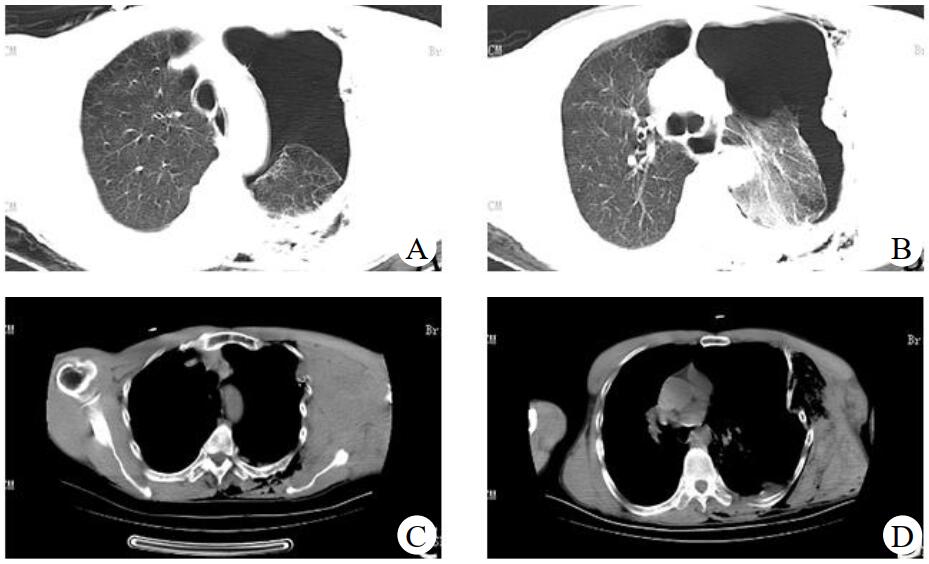

1 资料与方法患者,男性,54岁,因“重物砸伤致左侧肩部胸部疼痛、呼吸困难2 h”于2019年6月16日入院。患者2 h前在工地劳作时不慎被约20~30 kg重物砸伤,伤后即感左侧肩部胸部疼痛、呼吸困难,发病后无昏迷史、无恶心呕吐、无肢体抽搐、无大小便失禁。入院时查体:体温35.3 ℃,心率153次/min,呼吸27次/min,血压52/37 mmHg(1 mmHg=0.133 kPa),SpO2 77%(面罩吸氧5 L/min后上升至90%左右)。患者GCS评分15分,神志清楚,呼吸急促,左侧胸廓畸形,颈部、左前胸壁、左腋下、左上肢肿胀,左前胸壁可及皮下气肿,反常呼吸,四肢皮肤湿冷,左上肢活动障碍,桡动脉搏动较右上肢减弱,四肢末梢感觉无异常。急查床边超声示左侧胸腔积液,脾肾隐窝、腹腔未见明显积液。CT示颅内未见明显出血。左侧气胸伴左肺膨胀不全、挫伤,肺压缩约70%;左侧多发肋骨骨折,左侧颈部、胸部、侧胸部、背部皮下积气、血肿,见图 1。上下腹部未见明显外伤性改变。

| A、B:左侧气胸、左肺膨胀不全、左肺挫伤,C、D:左侧多发肋骨骨折、左侧胸背部皮下积气 图 1 患者急诊胸部CT |